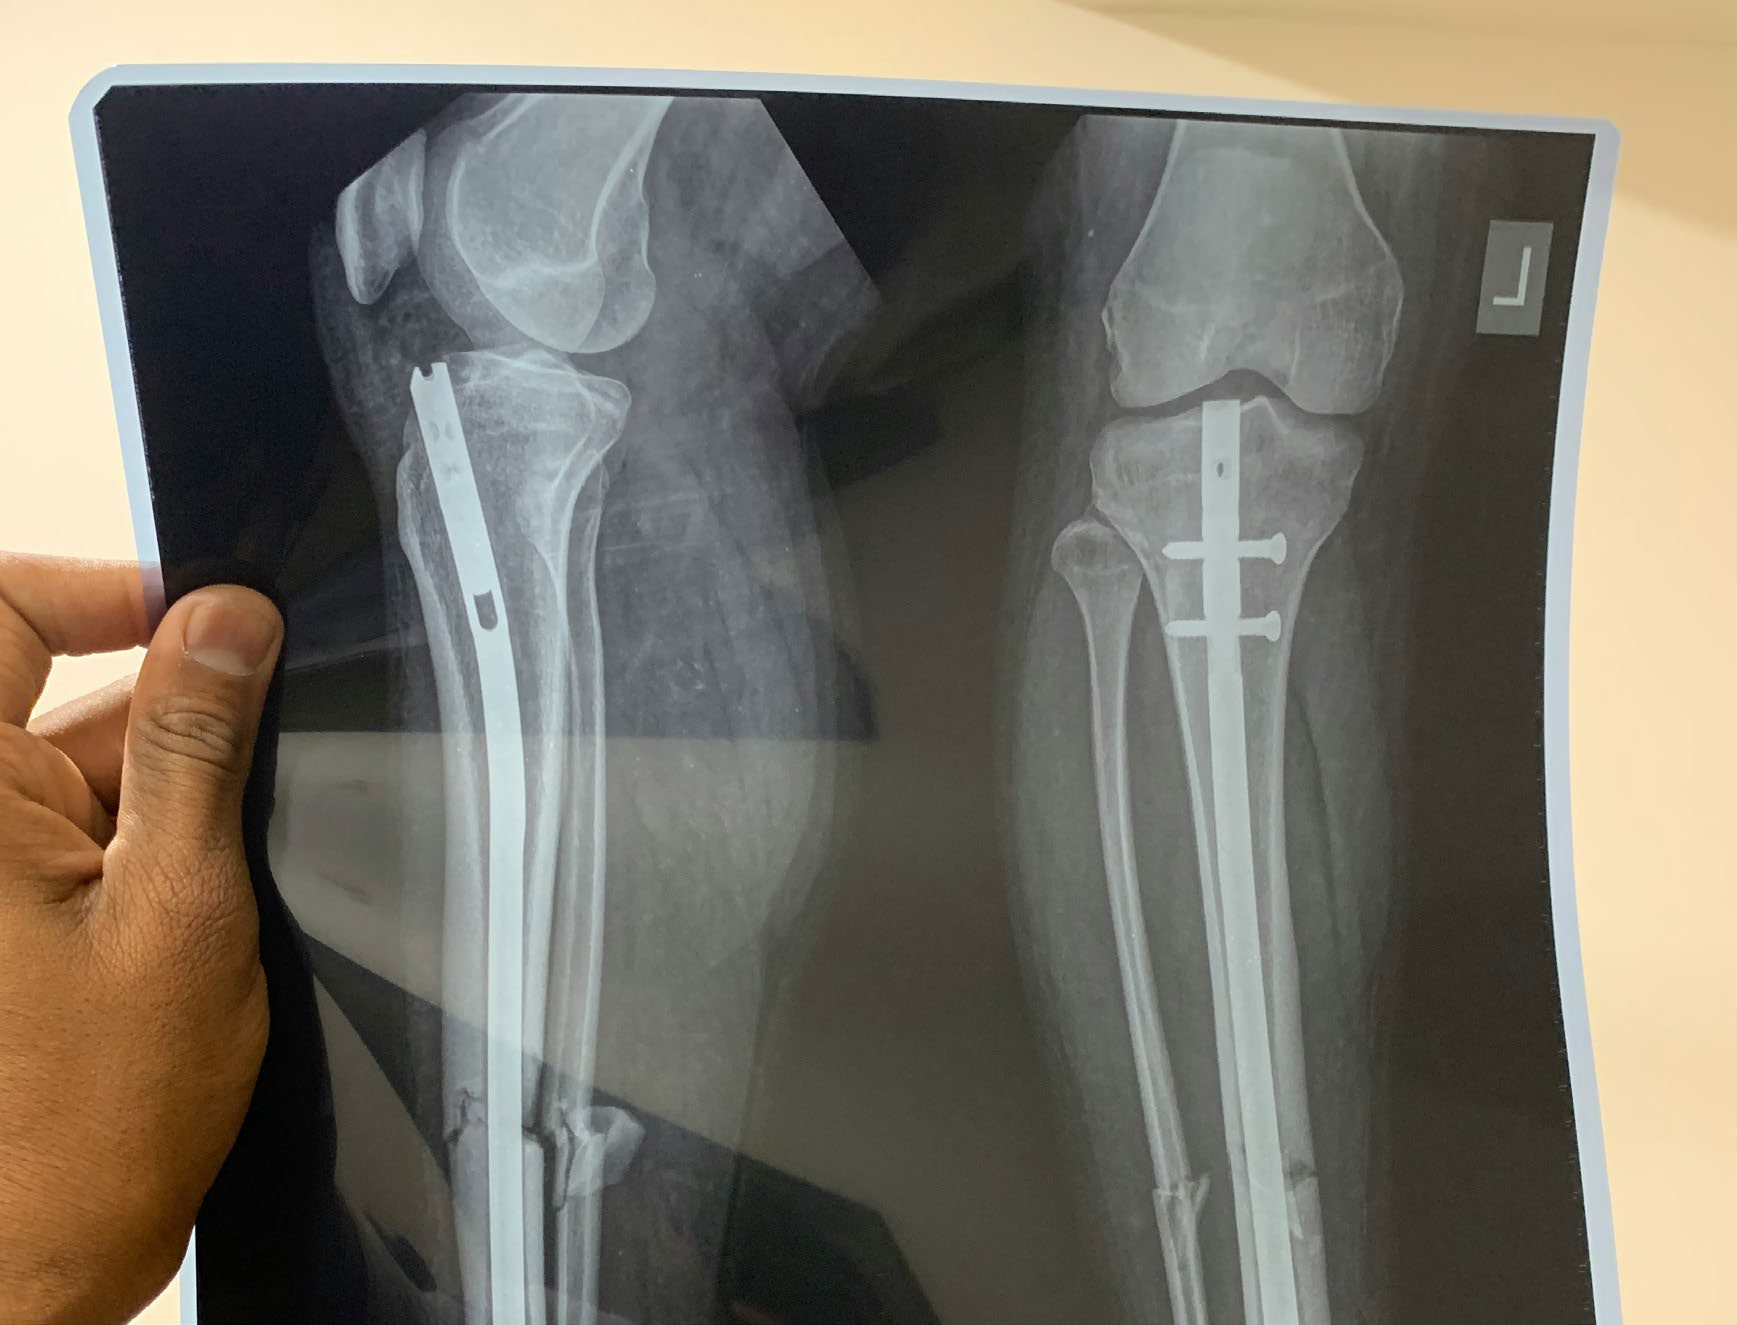

An X-ray of a leg showing surgical pins and a rod used to repair a break